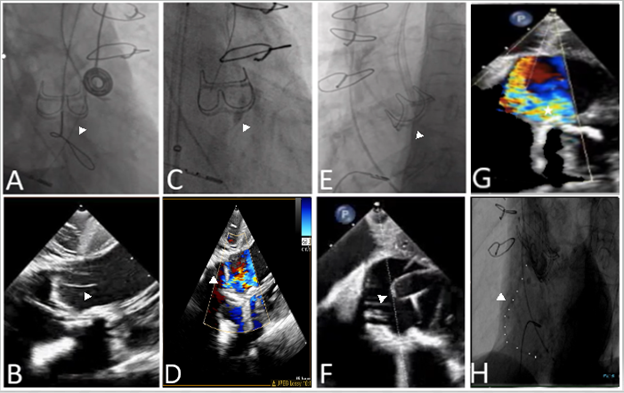

A 79-year-old man with a failed 25-mm CE Magna Ease 3300 surgical prosthesis (Edwards Lifesciences) and of high re-operative surgical risk (STS 8%) presented with dyspnea, NYHA III. Cardiac computed tomography angiography revealed anatomy that was at high risk for coronary occlusion with a short right coronary artery height of 6 mm and a valve-to-coronary distance of 2 mm. The decision was made for balloon-assisted BASILICA (bioprosthetic or native aortic scallop intentional laceration to prevent iatrogenic coronary artery obstruction during TAVR) and TAVR ViV using a 29-mm Evolut FX (Medtronic) under fluoroscopic and ICE guidance (Figure).

A 9-French VeriSight 3D ICE catheter (Phillips) was placed into the right atrium and a short axis view of the aortic valve was obtained. Three-dimensional ICE with x-plane and digital steering was able to identify the RCC, the ideal location for wire traversal (Figure A and B), and to visualize balloon dilatation (Figure C and D) and leaflet laceration (Figure E and F). Color Doppler revealed eccentric valvular aortic insufficiency through the right coronary leaflet (Figure G) and aortic root angiography confirmed patency of the RCA after TAVR (Figure H).